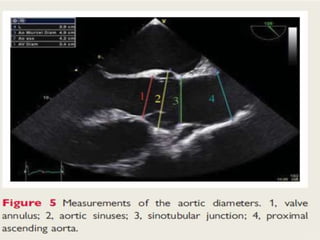

• 2.Dilation of the sinotubular junction – loss of the geometry of

aortic leaflet coaptation – jet arises centrally.